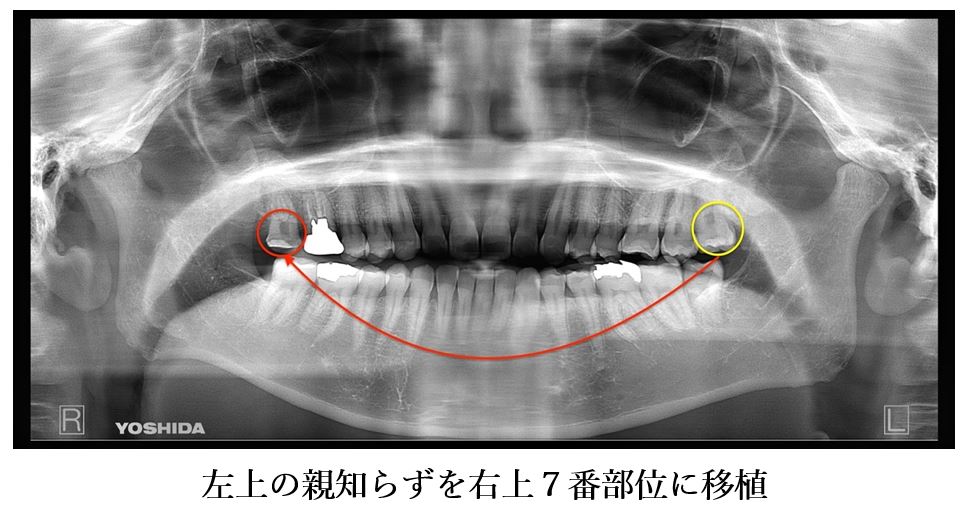

目白マリア歯科 親知らずの移植でインプラントを回避した症例_パノラマX線画像左上親知らずを右上7番部位に移植

患者様はインプラントを行うことには抵抗があり、抜歯後のプランに左上の親知らずを右上7番部位に移植することを選択されました。

左上の親知らずを抜歯後、すぐに右上7番部位に移植を施し2週間経過後に精密根管治療を行いました。